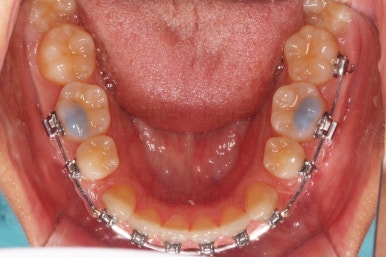

사용한 장치 : 자가결찰 금속(엠파워 메탈, Empower metal) + 미니스크류

초진 시 입안의 모습이에요. 치열이 많이 나쁜 편은 아니고 앞니쪽이 조금 삐뚤어져 있네요.

특히 윗니 작은 앞니 하나가 아랫니보다 안으로 쑥 들어가 있어서 옆에 있는 송곳니가 덧니처럼 보여요.

점점 이 뽑은 자리가 줄어가네요.

이 쯤 됨녀 중간평가를 해줘요.

자연스레 자리를 없애고 마무리를 할 것인지, 그것 보다 훨씬 더 많이 넣어볼 것인지, 아니면 오히려 앞으로 뺄지 말이죠.